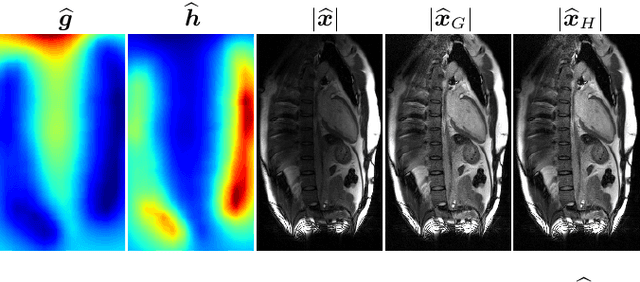

Abstract:Accelerated magnetic resonance (MR) imaging attempts to reduce acquisition time by collecting data below the Nyquist rate. As an ill-posed inverse problem, many plausible solutions exist, yet the majority of deep learning approaches generate only a single solution. We instead focus on sampling from the posterior distribution, which provides more comprehensive information for downstream inference tasks. To do this, we design a novel conditional normalizing flow (CNF) that infers the signal component in the measurement operator's nullspace, which is later combined with measured data to form complete images. Using fastMRI brain and knee data, we demonstrate fast inference and accuracy that surpasses recent posterior sampling techniques for MRI. Code is available at https://github.com/jwen307/mri_cnf/